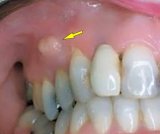

In the mouth, the healing phase presents as canker sores (aphthous ulcers) on the inside of the lips or cheeks, on the palate or tongue, or in all areas of the mouth, depending on the perception of the conflict situation (compare with aphthous ulcers related to the mouth surface mucosa). Canker sores appear as round or oval white spots with an inflamed border. They can be quite painful. On the gums, the pus-filled pocket is called a “dental abscess” or gum abscess. The tuberculous discharge causes bad breath.

If the required microbes are not available upon the resolution of the conflict, the additional cells remain. Eventually, the growth becomes encapsulated with connective tissue. In conventional medicine, this is usually diagnosed as a mouth polyp or “benign cancer”. A gum polyp might reach into the neck of a tooth.

In the nasopharynx, adenoids or nasal polyps that developed during the conflict-active phase are removed with the help of fungi or TB bacteria, provided they are available. The nasal discharge consists of smelly tubercular secretion. A nasal abscess with painful swelling containing pus also develops in the healing phase.